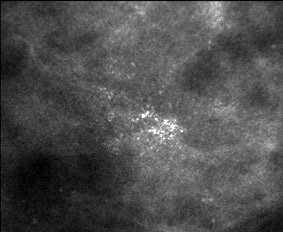

Las microcalcificaciones más que las

macrocalcificaciones, son las que se presentan más frecuentemente asociadas al

carcinoma y representan un gran problema diagnóstico. El análisis de las

calcificaciones en cuanto a su distribución,

tamaño, morfología y variabilidad, así como la presencia de hallazgos asociados,

como la ectasia ductal o un nódulo; nos permiten decidir cuáles son benignas, cuáles

deben ser seguidas cuidadosamente y cuáles deben ser biopsiadas.

Las calcificaciones malignas tienden a localizarse

en el interior de los conductos anormales y adoptan formas que son moldes del

revestimiento epitelial irregular del conducto. Las calcificaciones malignas

pueden ser identificadas cuando presentan un patrón lineal o ramificado, con

márgenes irregulares, dentados y definidos. Está indicada la biopsia cuando

descubrimos esta morfología en las mamografías.